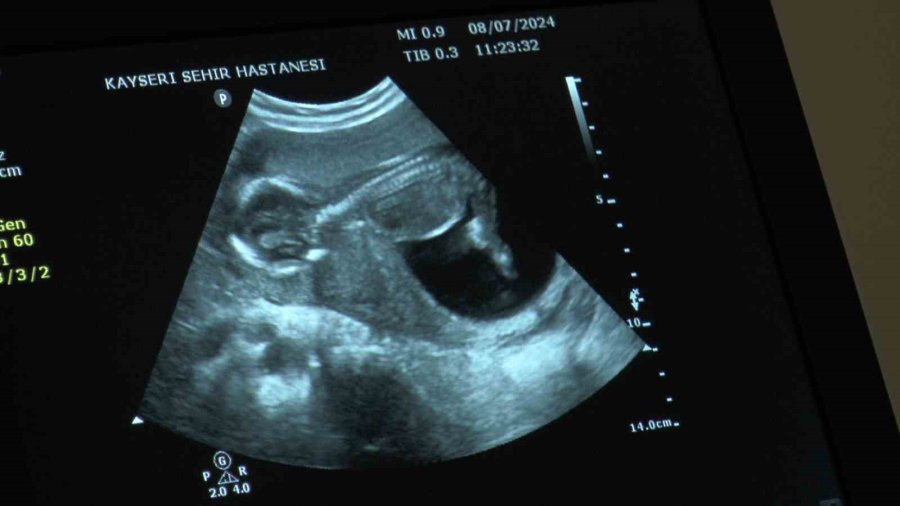

Kayseri'de yaşayan 1 çocuk annesi 35 yaşındaki S.D., ikinci kez anne olmak istedi. Fakat gittiği hastanelerde doğal yolla hamile kalmasının çok zor olduğu ve tüp bebek tedavisine yönelmesi gerektiği söylendi. En sonunda Kayseri Şehir Hastanesi'ne başvuran 35 yaşındaki S.D.'ye, doktorlar tarafından tüp bebek yönteminden önce tetkikler yapıldı. Kayseri Şehir Hastanesi Kadın Hastalıkları ve Doğum Kliniği Tüp Bebek Ünitesi'nde yapılan tetkiklerde daha önce düşük ve dış gebelik geçiren kadının rahim tüplerinden birinde tıkanma ve iltihaplanma olduğu tespit edildi. Yapılan ameliyat ile tıkalı tüpü alınan ve iltihapları temizlenen S.D., doğru tedavi yöntemi sayesinde tüp bebek ile değil doğal yolla kısa sürede ikinci çocuğuna gebe kaldı.

Doğru tedavi ve teşhis ile gebe kaldığını söyleyen S.D., "Buraya gelmeden önce dış merkezlerde birçok doktora gittim. Azalmış yumurta rezervimden ve yaş faktörümden dolayı normal yolla gebe kalamayacağımı ve zor olduğunu söylediler. Daha sonra Kayseri Şehir Hastanesi'ne geldim. Burada yapılan kontroller ve müdahaleler sonucunda aslında rahim tüplerimin birinde tıkanma ve iltihaplanma olduğu, tüp bebek de olsa tutunmayacağı ile bir an önce tedavi uygulanması gerektiği söylendi. Tetkikler sonucunda ameliyat oldum ve tüpümün biri alındı ve enfeksiyon temizlendi. 1 ay sonra da normal yolla gebe kaldım. Çok heyecanlıydım ve çok duygulandım. Güzel bir süreçti. Normalde burada tedaviye başlayacaktık ama normal yolla oldu. Şu an 16 haftalık hamileyim. Benim 2. bebeğim olacak, ilki 5 buçuk yaşında. Aslında şöyle, ben bir düşük geçirdim, daha sonrasında bir dış gebelik geçirdim. Tüpümde tıkanma olduğunu bilmiyordum. Buraya gelince öğrendim böyle bir şey olduğunu. Burayı çok beğendim. Doktorların ilgisi alakası gayet iyiydi. Bu konuda bana çok destek oldular. Doğru tedavi ve doğru teşhis ile hamile kaldım" dedi.

Doç. Dr. İlknur Çöl Madendağ,merkezde hastaya tedavi uygulamadan önce planlamaları yaparak bilgilendirdiklerini ve ortak karar ile tedavi uyguladıklarını söyleyerek, "Aslında hastalarımızın çoğu merkezimize tüp bebek yaptırma istemi ile gelmekte ama biz hastalarımızı değerlendirdikten sonra durumları hakkında ayrıntılı bilgi verip, tabi son tercihi onlara bırakmakla beraber, bilimsel veriler ışığında tıbbi durumu ne gerektiriyorsa öncelikle onu öneriyoruz hastalarımıza. Öncelikle tıbbi durumu hakkında hastalarımızı bilgilendirip önerimizi yapıyoruz ve onun isteği ile ortak kararımızı verip tedavimizi uyguluyoruz. Burada da hastamızın azalmış yumurtalık rezervi dediğimiz yumurta sayısı azlığı ve geçirilmiş dış gebelik, düşük, rahim tüp iltihabı, enfeksiyon durumları gibi sıkıntıları vardı. Bize geldiğinde önce ayrıntılı muayenesini yapıp gerekli tetkiklerinin ardından cerrahi müdahalesini planladık. Hastamızın azalmış yumurta sayısı vardı ama öncelikle rahim tüp filmini çektiğimize tüplerinde sıvı toplaması olduğunu ve kapalı olduğunu gördük. Yaptığımız ameliyatta tüpünün tıkalı olduğunu teşhis edip o sıvı toplamış tüpü aldık. Diğer tüpünün açık olduğunu gördükten sonra enfeksiyon tedavisini de yaptık. Yumurtalık gelişimini ve zamanlamasını ayarlayarak tüp bebek tedavisine gerek kalmadan gerekli antibiyotedavisini de verdikten sonra spontan gebeliğe 2 ay gibi kısa bir zaman içinde ulaştık. Geçirilmiş iltihabı vardı ve buna bağlı dış gebeliğinin oluştuğu yerde sıvı toplaması vardı. Bu da engel olan bir durumdu. Sonrasında hastamızın yumurta sayısını tekrar saydık. Gerekli destek tedavilerini verdik ve gebeliğine ulaştık. Şu an 16 haftalık gebeliği mevcut ve sağlıklı bir şekilde gidiyor" dedi.